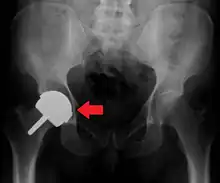

Dislocated artificial hip

Liner wear, particularly when over 2 mm, increases the risk of dislocation.[8] Liner creep, on the other hand, is normal remoulding.[9]

Dislocation (the ball coming out of the socket) is the most common complication. The most common causes vary by the duration since the surgery.

Hip prosthesis dislocation mostly occurs in the first three months after insertion, mainly because of incomplete scar formation and relaxed soft tissues.[8] It takes eight to twelve weeks for the soft tissues injured or cut during surgery to heal. The chance of this is diminished if less tissue is cut, if the cut tissue is repaired and if large diameter head balls are used.